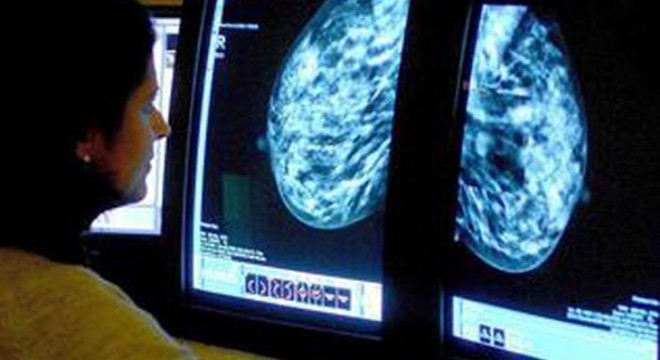

‘Meme kanserinde elle muayene yeterli değil’

Türk Cerrahi Derneği Başkanı Prof. Dr. Çağatay Çifter, “Meme kanserinde erken teşhis için kullanılan ‘kendi kendine muayene’ kanser tedavisinde gecikmeye neden olabilir” dedi.

Avrupa’da yüzde üç olan meme kanseri görülme oranı Türkiye’de yüzde 17’ye yükseliyor. Aradaki fark, ölümlere neden olan meme kanserini ülke için önemli bir sorun haline getiriyor. Meme kanseri teşhisi konusunda açıklamalarda bulunan Türk Cerrahi Derneği Başkanı Prof. Dr. Çağatay Çifter şunları söyledi:

“Kendi kendine muayenenin meme kanserinde ölüm oranlarında düşüş sağladığını gösteren hiçbir bilimsel çalışma yok. Bu tür muayene her ne kadar zararlı bir yöntem değilse de psikolojik stres yaratabilmesi hem de gereksiz tetkiklere yol açabilmesi açısından eleştiriliyor. Ayrıca, eğitimsiz bir el tarafından yapıldığından bir çok lezyon gözden kaçırılarak ‘normal meme’ olarak değerlendirilebiliyor. Meme kanserinin biyolojik gelişimine baktığımız zaman, tek bir hücreden başlayıp bir santimetre çapa ulaşabilmesi için yaklaşık 7 yıl geçmesi gerektiğini görüyoruz. Kanser, ancak 0,5 santimetre çapa ulaştıktan sonra uzak organlara yayılım yeteneği kazanabiliyor. Tecrübeli doktorların bile muayenede bir kitleyi fark edebilmeleri için, çapının en az bir santimetre olması gerekiyor. Tıp eğitimi almamış bir kişinin kendisini muayene ederek bulabileceği bir meme kanserinin en az 2-3 santimetre çapında olabileceği aşikar ve bu büyüklüğün altındaki bir kitlenin fark edilmesi mümkün görünmüyor.

RUTİN KONTROLÜ YAPTIRIN

Kendi kendine muayene ile bulunan bir meme kanseri ‘erken meme kanseri’ değil. Biliyoruz ki erken tanı konulabilmesi halinde meme kanseri tedavi edilebilir bir hastalık. Risk altındaki grupların yıllık doktor ve görüntüleme kontrollerine gitmeleri gerekiyor. Yapılan birçok çalışmada, meme kanseri kendisi tarafından fark edilen hastaların, rutin taramalarla meme kanseri tanısı konulanlara göre yaşam sürelerinin ‘daha kısa olduğu’ görülüyor. Meme kanseri tanısının, hastanın kendi kendini muayenesinde fark edemeyeceği bir boyuttayken konulması hayat kurtarıcı. Meme kanserinden korunma yolu kendi kendine muayene değil, rutin doktor kontrolüdür.”